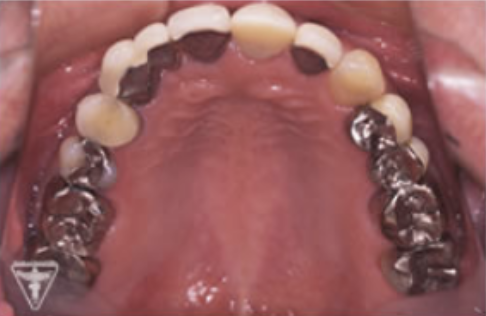

治療前

初診時の正面観・側方観・かみ合わせの面の状態を示します。

下の顎のずれがあるのを確認して下さい。